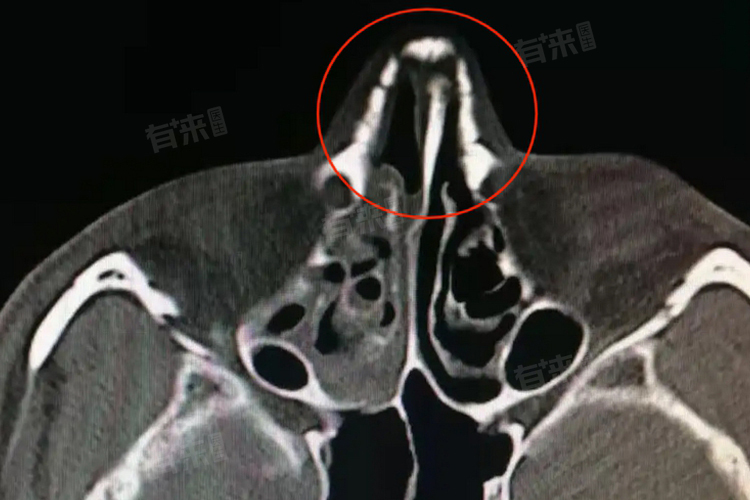

鼻骨粉碎性骨折是否手术取决于骨折严重程度、患者功能需求及整体健康状况。严重畸形、影响通气或有特定需求可能需手术,医生会谨慎评估,手术包括鼻骨复位术和鼻整形术,以恢复结构与改善外观。

- 骨折的严重程度是重要的考量因素,如果鼻骨粉碎性骨折导致了明显的鼻部畸形,如鼻梁塌陷、歪斜等,通常需要手术进行矫正。严重的畸形不仅影响外观,还可能影响鼻腔的通气功能。如果骨折碎片移位明显,可能会压迫周围的组织和神经,引起疼痛、肿胀、鼻出血等症状,这种情况下也需要手术治疗。